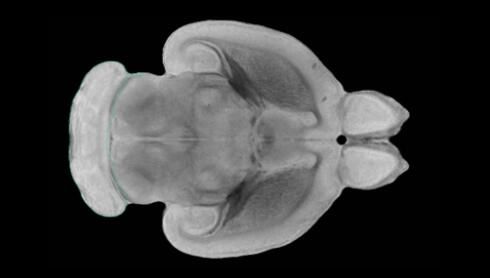

隨著機(jī)體年齡增加,肌肉和關(guān)節(jié)都會(huì)變得僵硬,這就會(huì)使得日?;顒?dòng)變得更加困難,本文研究表明,我們的大腦也是如此,與年齡相關(guān)的大腦僵硬對(duì)大腦干細(xì)胞的功能或許有著重要影響。文章中,研究人員對(duì)年輕和老化大鼠的大腦進(jìn)行研究闡明了年齡相關(guān)大腦僵硬對(duì)少突膠質(zhì)前體細(xì)胞(OPCs,oligodendrocyte progenitor cells)功能的影響。OPCs是一類對(duì)維持正常大腦功能非常重要的大腦干細(xì)胞,其對(duì)于髓磷脂的再生也非常重要,髓磷脂是神經(jīng)組織周圍的脂肪鞘,在多發(fā)性硬化癥中髓磷脂的再生常常會(huì)被損傷,機(jī)體老化對(duì)這些細(xì)胞的影響常常會(huì)誘發(fā)多發(fā)性硬化癥的發(fā)生,這些細(xì)胞的功能在老化的健康人群中同樣會(huì)下降。

為了確定老化OPCs的功能缺失是否可以被逆轉(zhuǎn),研究人員將來自老化大鼠機(jī)體的老化OPCs轉(zhuǎn)移到了年輕大鼠柔軟的海綿狀大腦組織中去,值得注意的是,這些老化的大腦細(xì)胞能夠重新恢復(fù)活力,其行為非常像年輕更加強(qiáng)壯的細(xì)胞。這項(xiàng)研究中,研究人員在實(shí)驗(yàn)室中開發(fā)出了具有可變僵硬程度的新型材料,并在受控環(huán)境下研究這些材料的生長(zhǎng)及其對(duì)大鼠大腦干細(xì)胞的影響,這些材料能被工程化改造具有和年齡或老化大腦相似的柔軟程度。

為了深入理解大腦組織柔軟和僵硬影響細(xì)胞行為的分子機(jī)制,研究人員對(duì)細(xì)胞表面一種名為Piezo1的蛋白質(zhì)進(jìn)行了分析,該蛋白質(zhì)能“告知”細(xì)胞其周圍的環(huán)境為柔軟或僵硬。研究者Kevin Chalut說道,我們發(fā)現(xiàn),當(dāng)在僵硬材料上促進(jìn)年輕具有功能性的大鼠干細(xì)胞時(shí),這些細(xì)胞就會(huì)表現(xiàn)出功能異常,并失去其再生的能力,實(shí)際上其行為與老化細(xì)胞相似。當(dāng)將老化的大腦細(xì)胞在柔軟材料上生長(zhǎng)時(shí),其功能就會(huì)表現(xiàn)得像年輕細(xì)胞一樣,換句話說,其能夠重新恢復(fù)年輕的活力。